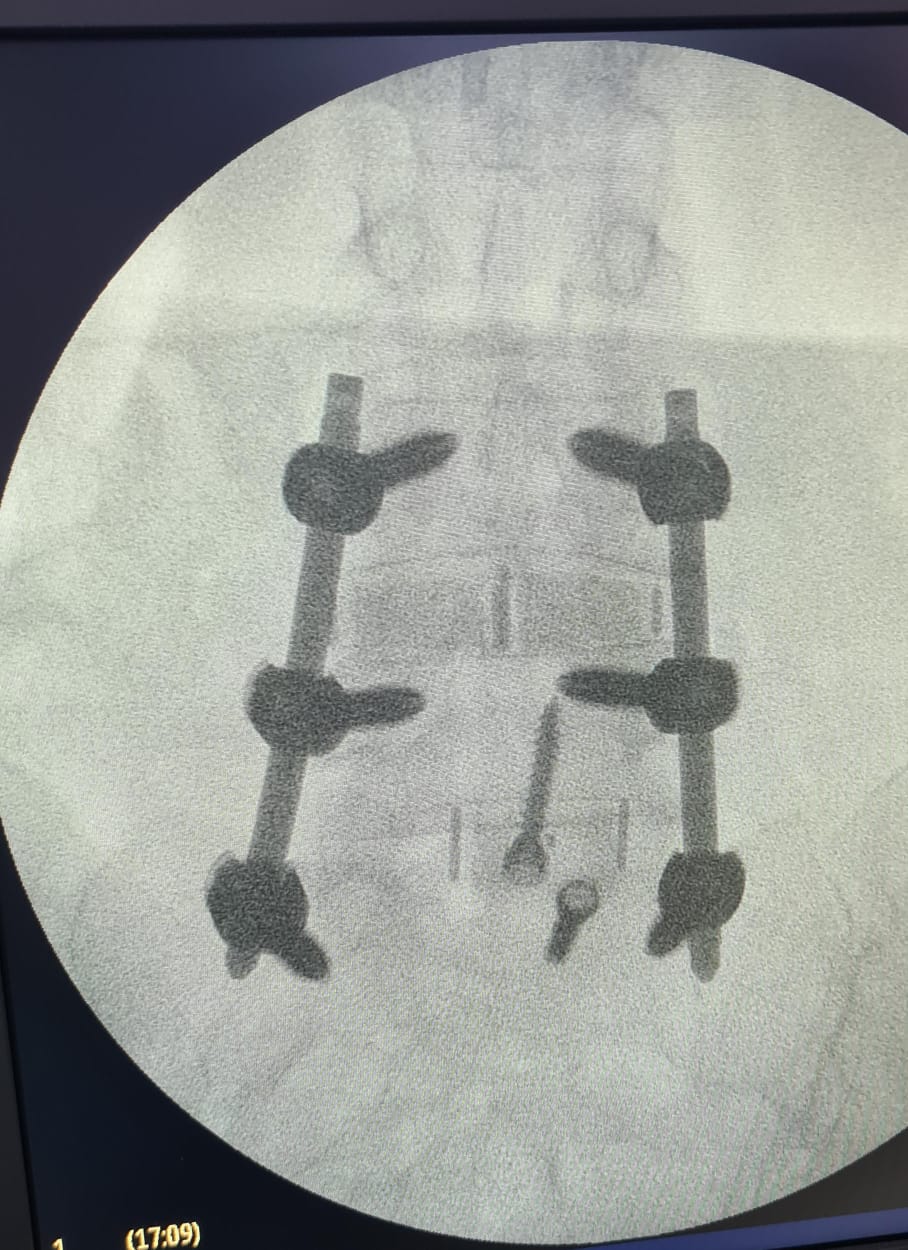

“Fueron tres tipos de exposiciones. Una de ellas es la cirugía en vivo, donde realizamos dos procedimientos en pabellón, acompañados por destacados especialistas, el Dr. Carlos Zanardi, presidente de la Sociedad de Neurocirugía de Buenos Aires, Argentina y el Dr. Cristiano Meneses, director del Instituto de Columna de Brasil”, precisó el Dr. Muñoz.

A continuación, compartimos las fotografías enviadas por el Dr. Avaria a la Sociedad de Neurocirugía de Chile: